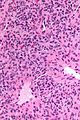

| LM | fascicular pattern (may be subtle) with compressed blood vessels (often thin walled & branching), increased peri-vascular cellularity; high cellularity; small bland unequally spaced epithelioid/spindle cells with moderate eosinophilic cytoplasm |

- Fascicular pattern - may be subtle - with:

- Compressed blood vessels, often thin walled & branching.

- Increased peri-vascular cellularity.

- Cellular lesion:

- Small bland unequally spaced epithelioid/spindle cells.

- Moderate eosinophilic cytoplasm.